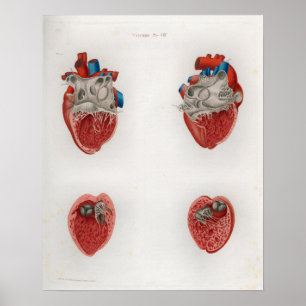

Poster 1833 interno da anatomia do coração do

Preço36,00 €

Póster O coração e as artérias bronquiais

Preço80,00 €